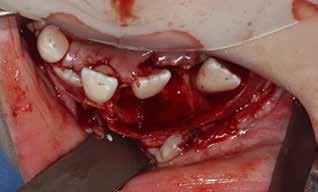

PATIENTTILFÆLDE 1

Patienttilfælde 1 (Fig. 1) er en 37-årig kvinde, henvist efter succesfuld behandling af stadie 3-parodontitis. Der er nu sundt

Før behandling

parodontium, ingen pocher over 4 mm, og både blødnings- og plakindeks er under 10 %. Patienten er motiveret for ortodontisk behandling, da hendes tænder er vandret over tid, delvist som følge af reduceret parodontium.

Der ses anterior trangstilling i begge kæber og overerupterede 1+1 og 2,1-1,2, hvilket resulterer i dybt bid med 2- tæt på ganepåbidning. Der er normale sidetandsrelationer, men der ses 5 mm horisontalt overbid (HOB) og 7 mm vertikalt

overbid (VOB). Papillen mellem 1+1 er betydeligt reduceret pga. fæstetab, og de mesialt kippede 1+1 har resulteret i en ”dark triangle”. Den facioorale funktion er for nuværende i.a. Panoramarøntgen (Fig. 1, I) viser marginalt knogletab i begge kæber og fravær af 8,7+7,8 og 8,7-8.

Der planlægges alignerbehandling af begge kæber med intrusion af 1+1 og 2,1-1,2, nivellering af trangstilling UK med interproksimal reduktion (IPR) (Fig. 2 A, B) og senere IPR OK for reduktion af dark triangles mellem incisiverne efter nivellering. Patienten instrueres i at benytte alignere 20-22 timer/ dag med alignerskift hver 7. dag, og patienten ses hver 3.-8. uge under forløbet. Den første alignerserie består af 16 alignere for nivellering OK/UK og IPR i UK (Fig. 2). Efter denne serie planlægges IPR mellem incisiverne i OK for reduktion af dark triangles (Fig. 3) samt yderligere intrusion af OK og UK-fronten i 12 refinement-alignere. Patienten udviser god kooperation og er meget tilfreds med alignerapparaturet, som er mindre synligt end det faste apparatur (Fig. 4).

Behandlingen afsluttes med yderligere refinement-alignere for finindstilling af okklusionen, og efter 11 måneders ortodontisk behandling er der opnået normale relationer i alle tre